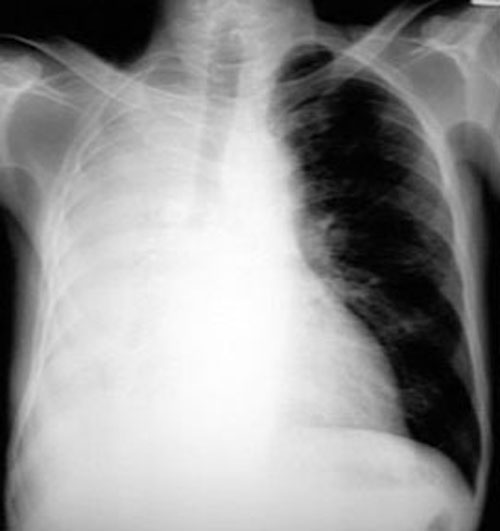

Resorptive atelectasis When airways are obstructed there is no further ventilation to the lungs and beyond. In the early stages blood flow continues and gradually the oxygen and Nitrogen get absorbed, resulting in atelectasis. The following in an example of right lung resorptive atelectasis. In this instance, atelectasis followed bronchial obstruction due to cancer. Lung is not permitted to assume complete atelectatic state as occusr in pneumothorax as it is held by the negative pressure in pleura. Some amount of fluid exudes into alveoli, and thus it is not completely empty. |